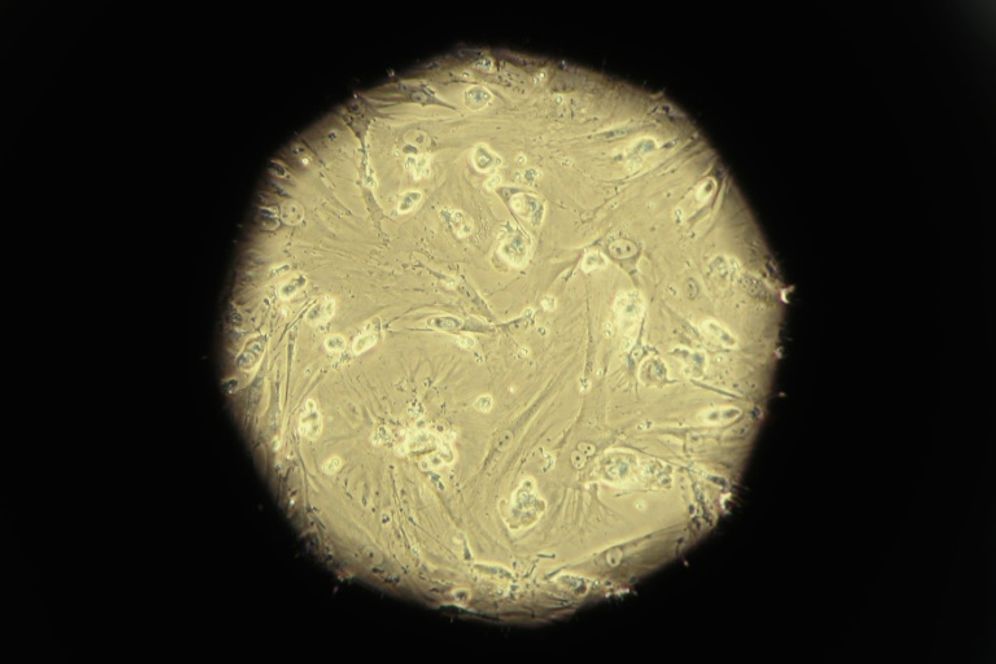

Un laboratoire de l'institut Weizmann est parvenu à produire des embryons de souris synthétiques sans ovule et sans sperme, uniquement à partir de cellules souches prélevées sur la peau.

Cette percée, publiée lundi dans la revue Cell, constitue une première. Jamais auparavant un embryon avancé de n'importe quelle espèce n'avait pu être créé à partir de cellules souches seules.

Les embryons comportant un cerveau au stade précoce et un cœur battant ont été formés après seulement huit de jours de mise en culture des cellules souches, soit un tiers de la période de gestation d'une souris. Ils ne sont toutefois pas viables pour d'éventuelles transplantations, selon le laboratoire.